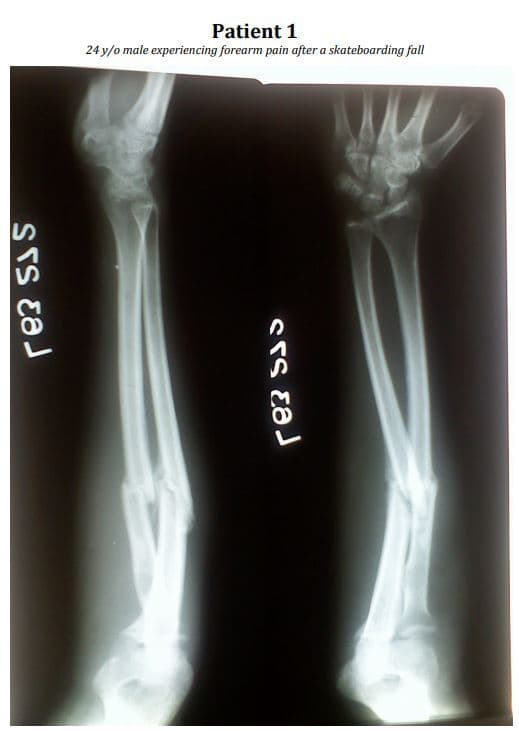

Are these bones axial, appendicular, or both?

How would you describe the fracture?

Name the type of fracture

List ALL of the bones present.

What may have caused this abnormality?